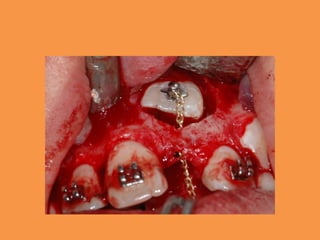

Figure 4: Surgical exposure of 11

Figure 5: Intraoral view showing the

Figure 4: Surgicalexposure of 11

• 30.